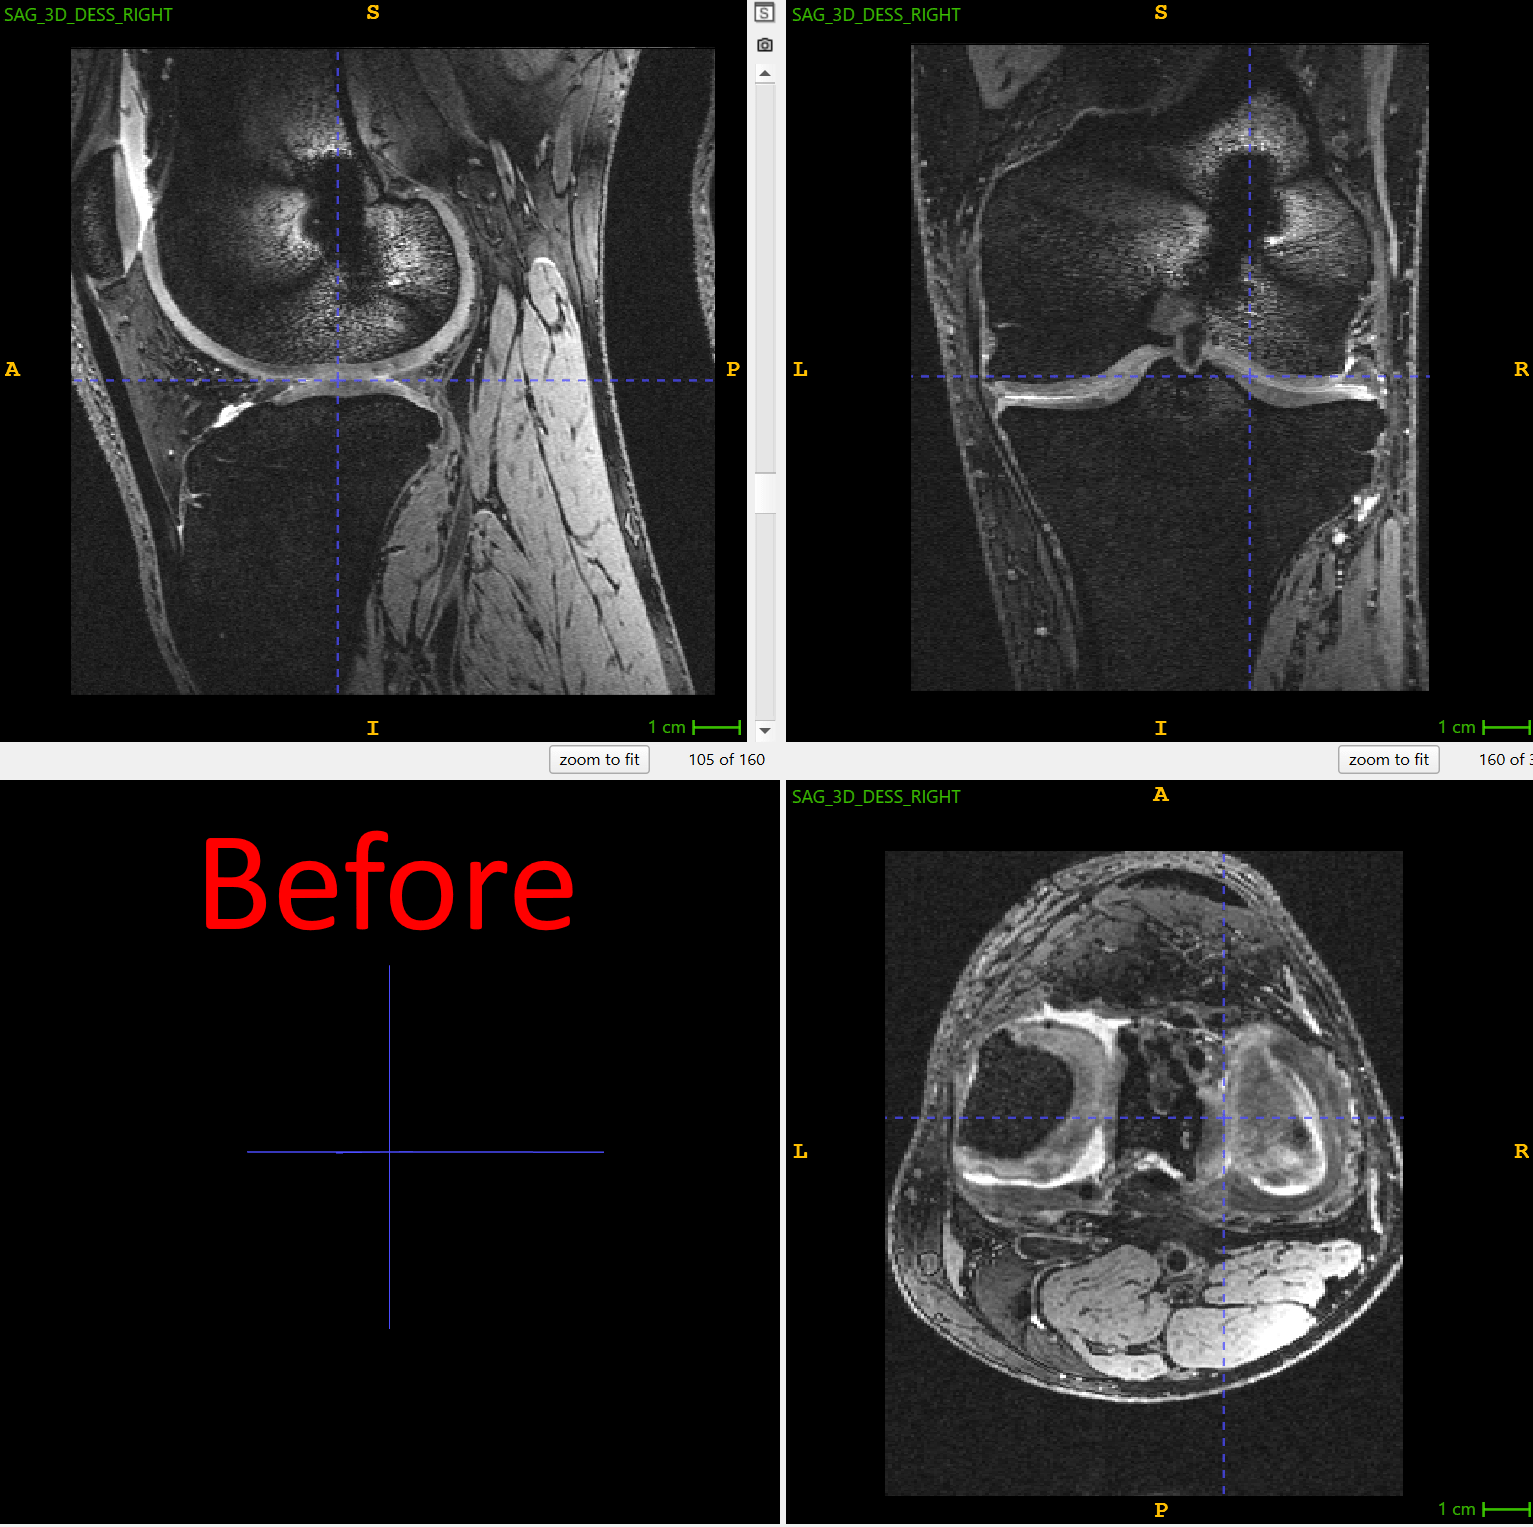

Consider a deep learning pipeline that we built in collaboration with UNC for osteoarthritis research, where knee MRIs from thousands of patients must be analyzed for cartilage thinning. Neural networks are sensitive to the orientation of their inputs. If one dataset encodes knees in left–right orientation and another in posterior–inferior orientation, the model may learn misleading features or fail.

In the same processing step, we applied a left–right mirroring operation, ensuring that all right knees are flipped to match a left-knee atlas. What appears to be a trivial preprocessing step is actually a key enabler of deep learning: by reliably standardizing orientation, ITK removed variability in the data, allowing the neural network to focus on learning biological patterns rather than scanner artifacts.

Figure 1: right knee is mirrored to match the atlas in the orientation of the left knees. Screenshots made using ITK-SNAP, one of the end-user applications built on top of ITK library. Use left-right slider to compare before vs. after.